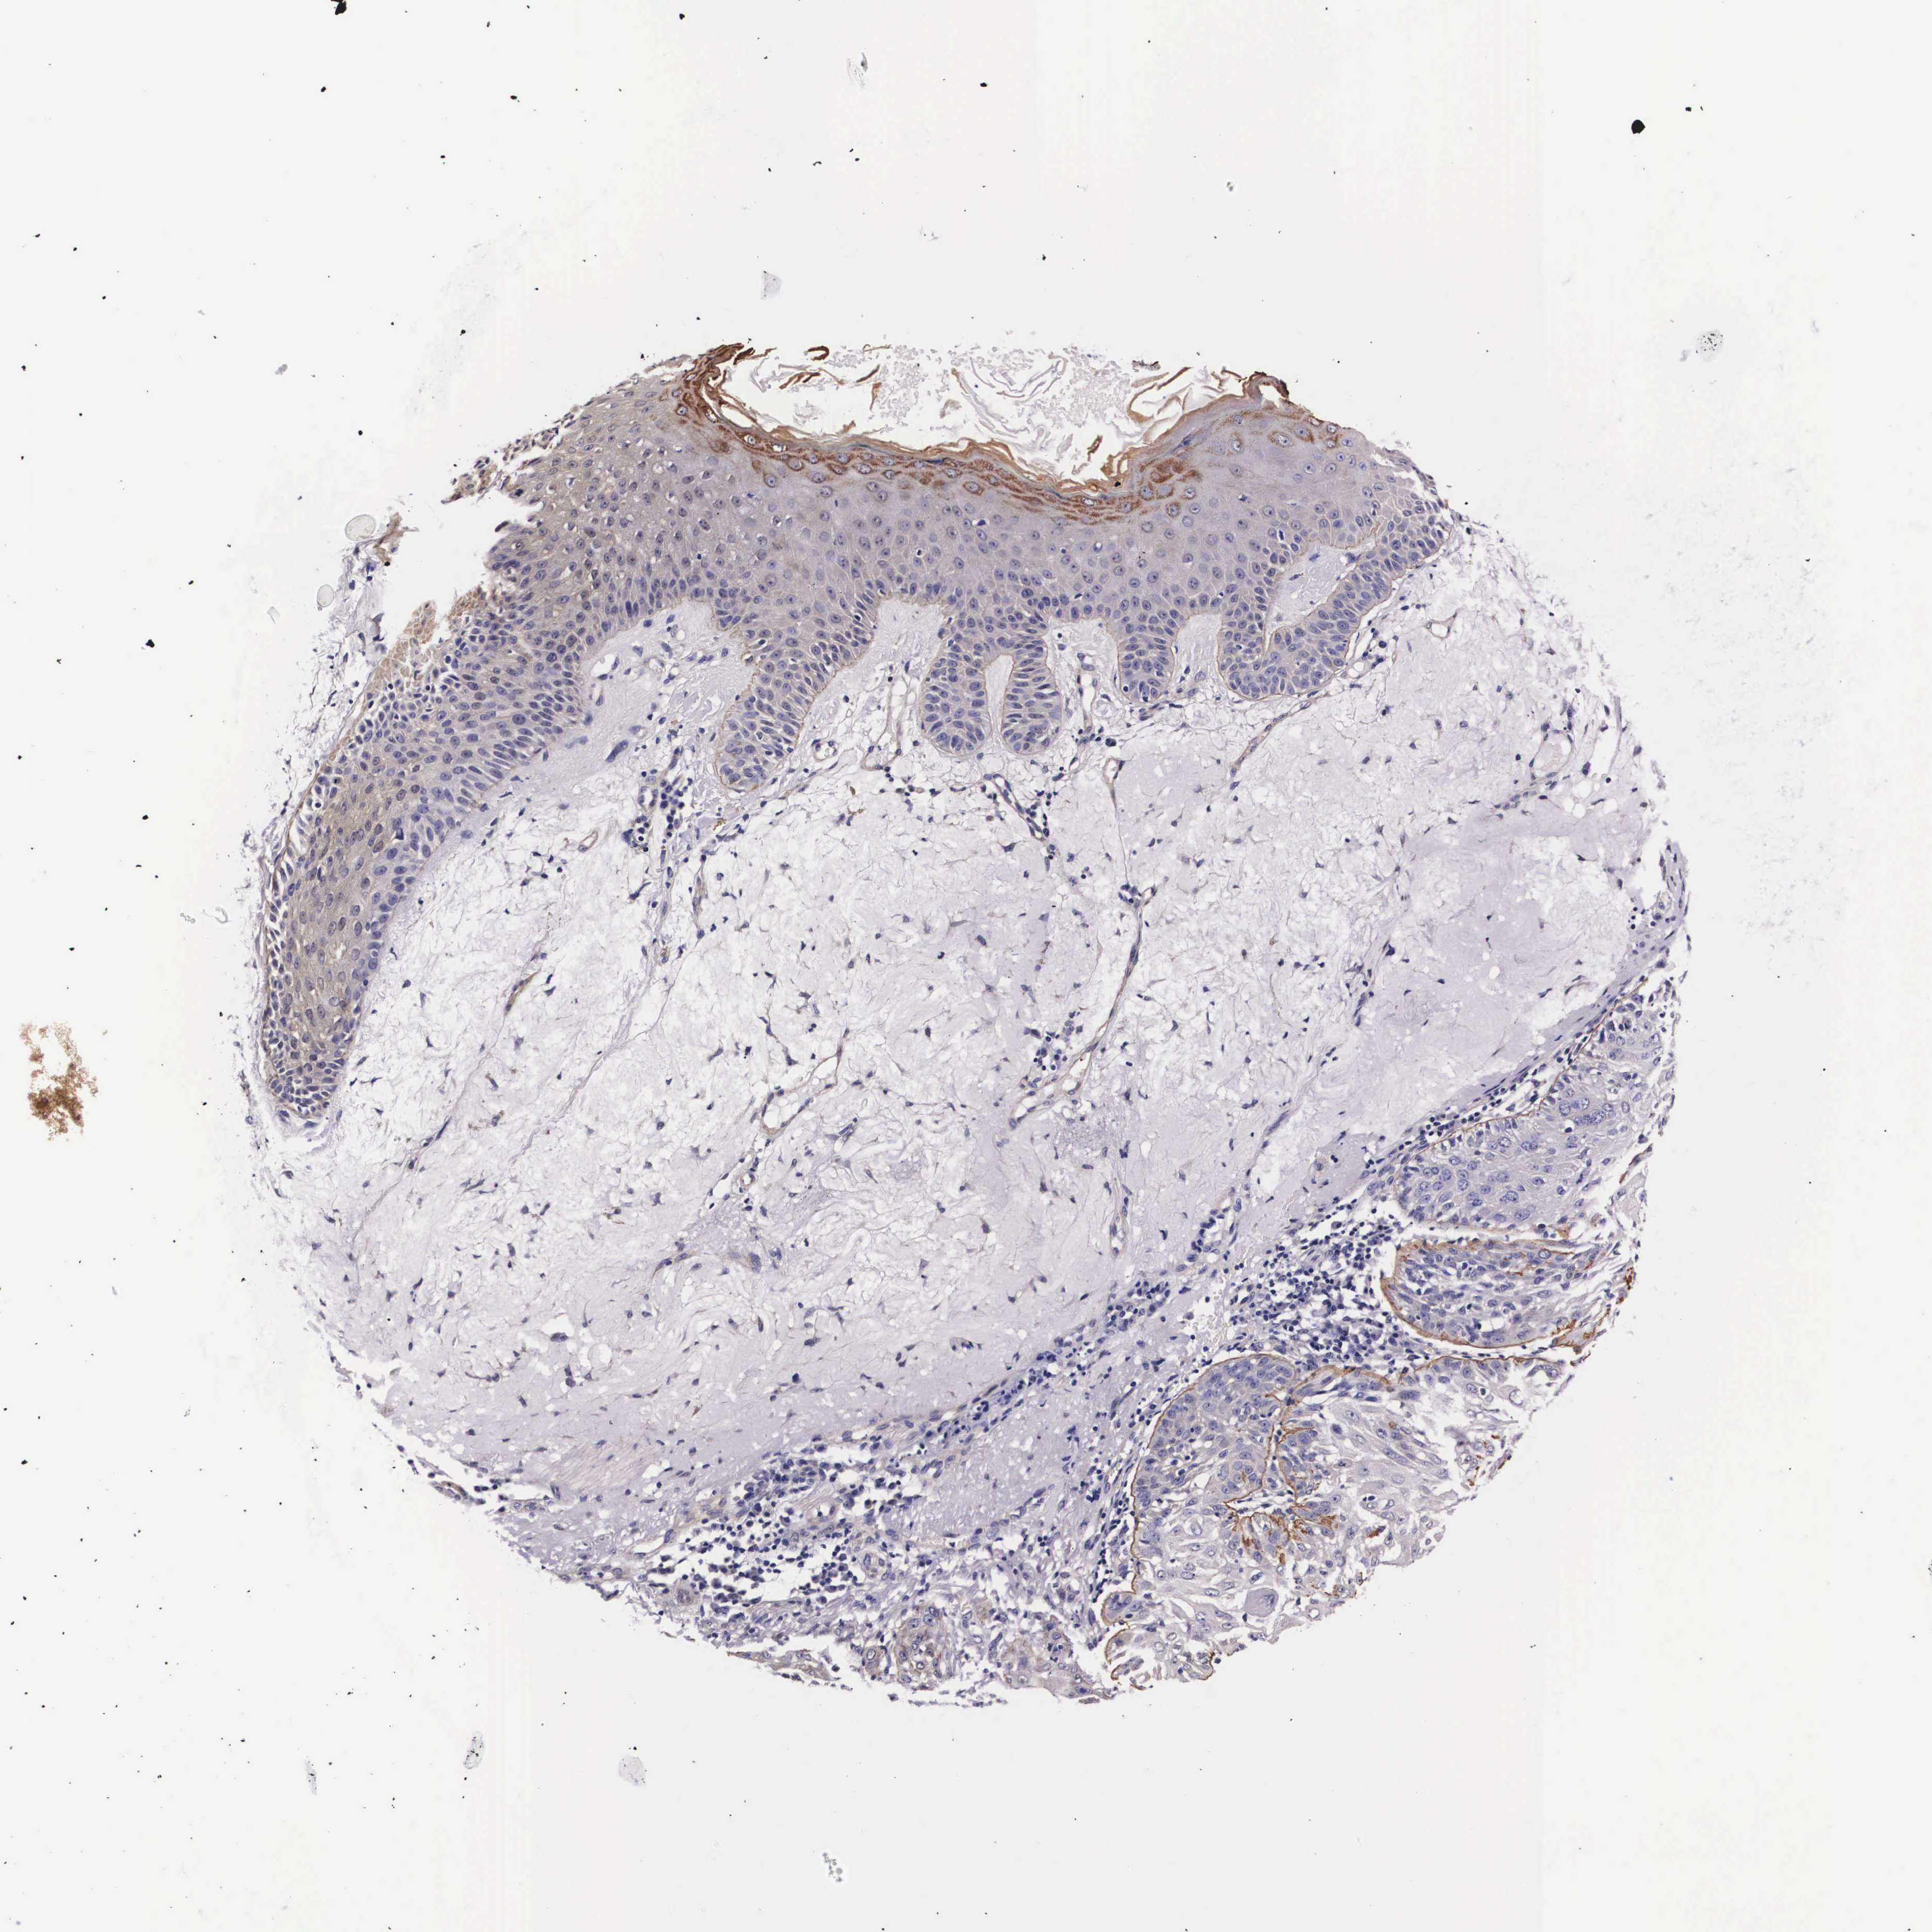

SKIN CANCER - Protein expressioni

A mouse-over function shows sample information and annotation data. Click on an image to view it in a full screen mode. Samples can be filtered based on level of antibody staining by selecting one or several of the following categories: high, medium, low and not detected. The assay and annotation is described here.

Antibody stainingi

Antibody staining in the annotated cell types in the current human tissue is reported as not detected, low, medium, or high, based on conventional immunohistochemistry profiling in selected tissues. This score is based on the combination of the staining intensity and fraction of stained cells.

Each image is clickable and will lead to virtual microscopy that enables deeper exploration of all samples and also displays staining intensity scores, fraction scores and subcellular localization as well as patient and tissue information for each sample.

Antibody HPA000647

Staining

High

Medium

Low

Not detected

Intensity

Strong

Moderate

Weak

Negative

Quantity

>75%

75%-25%

<25%

None

Location

Nuclear

Cytoplasmic/membranous

Cytoplasmic/membranous,nuclear

Squamous cell carcinoma, NOS

Basal cell carcinoma